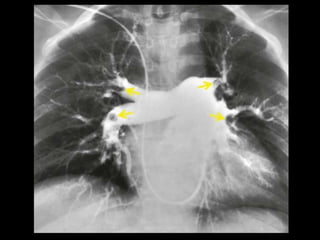

Êmbolo Séptico Embolia pulmonarséptica se apresenta com quadro insidioso de febre, tosse e opacidades pulmonares; Comumente visto em portadores de cateteres permanentes, endocardite da tricúspide, etilismo, infecções de pele e usuários de drogas IV; Manifestação radiográfica: opacidades nodulares bilaterais, com dimensões variadas que, em geral, apresentam escavações; A embolia séptica é com frequência complicada com empiema.

• 45.

Êmbolo Séptico TC: modalidade importante para confirmar a presença de êmbolos sépticos quando a radiografia convencional de tórax permanece negativa; TC: nódulos bilaterais mais numerosos nas regiões periféricas dos pulmões e nas bases; Os nódulos podem ser bem circunscritos ou mal definidos e com frequência apresentam escavações; O sinal do vaso nutriz pode estar presente em 60- 70% dos casos.